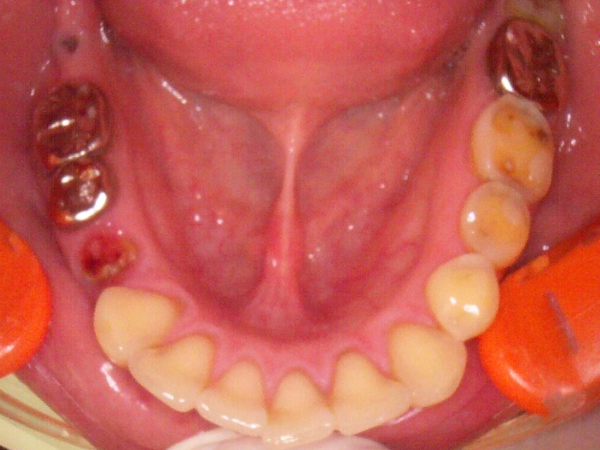

正確な診断が行えるよう歯科用CTを導入し、治療の精度を上げるための工夫をしております。

インプラント治療は、見た目だけでなく噛む力の回復やお口全体の健康にもつながる治療です。